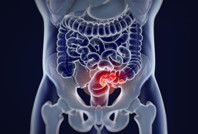

50 yaş altı kadınlar dikkat: Kanser riskini artırıyor Yeni bir araştırma 50 yaş altı bireylerde artan kolorektal kanser riskinin sebeplerinden birini ortaya çıkardı.